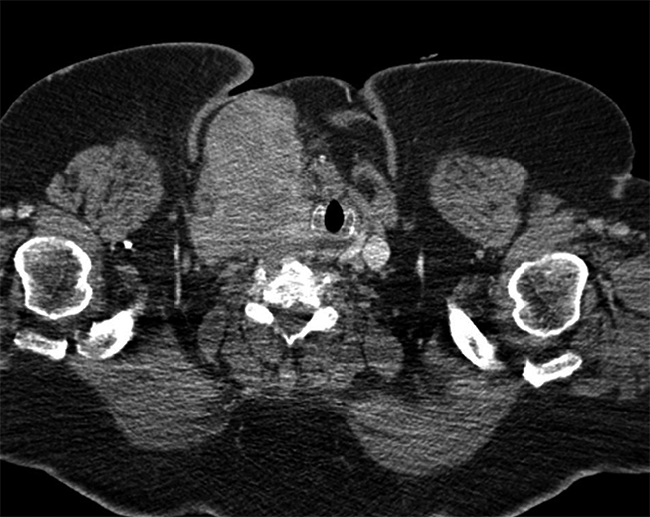

Se realiza angiotomografía craneal y cervical, que revela gran masa cervical derecha de origen tiroideo con realce heterogéneo de 95 x 67 x 82 mm, la cual compromete músculos esternocleidomastoideo y platisma, desplazando la tráquea (Figura 1). Adenopatías cervicales GI y GIIa de hasta 11 mm, trombosis del seno transverso, sigmoideo (Figura 2a) y vena yugular derecha. Lesiones líticas en región pretroclival de 17 mm que contacta región posterior de seno cavernoso y canal medular (Figura 2b). Tomografía de tórax: 5 nódulos pulmonares indeterminados de 3-4 mm, adenopatías cervicales inferiores, retrotraqueales y masa tiroidea previamente descrita que se extiende hacia tórax. Estudio tiroideo: TSH 4,47 ulU/ml; T4 Libre 1,24 ng/dl, anticuerpo antitiroglobulina 25 UD OMS y tiroglobulina 763 ug/L.